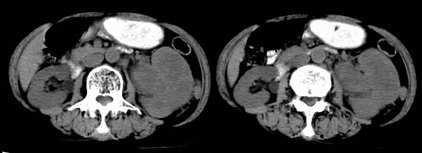

左肾不规则软组织肿块,内见低密度坏死区,与正常肾实质分界不清,左肾明显增大,增强呈不规则条索状强化,肾盂及左输尿管上段扩张。肾周脂肪层受侵、模糊。印象:典型左肾癌。

平扫,表现为肾实质肿块,呈分叶状,肿块密度不均,内有不规则低密度区(陈旧性出血?坏死?)有的似呈囊性,增强明显不均一强化,与肾实质相比呈相对低密度的不均一肿块,肾周脂肪间隙可见,肾前筋膜未见增后,肾血管及腹主动脉旁未见肿大淋巴结影

三期抓的不错,典型的肾癌,且已累及肾盂及左输尿管上段